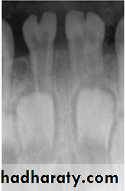

• Fusion of the left mandibular central and lateral incisors (twoindividual roots, two root canals and two joined crowns).

Gemination of right mandibular central incisor has one root, one root canal and a partially bifid dental crown.